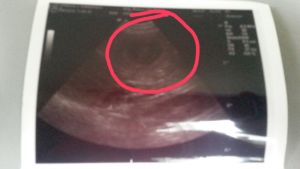

Röntgentermin beim Tierarztteam Jörn Emmerich in Vallendar 08. Januar 2014 Also ... gestern war es soweit und wir haben ein gaaaanz spezielles Bild von Keks geschossen. Zuerst war ich zwar etwas irritiert, dass das Bild mit Keks allein (ohne mich) gemacht wurde, aber der Maus ging es die ganze Zeit sehr gut und sie war auch ganz brav!!! Nach dem Bild durfte ich zur Besprechung rein. Herr Emmerich ist von Keks´ körperlichem und gesundheitlichen Zustand begeistert und er sieht keinerlei Probleme auf uns zukommen. Nichts desto trotz stehen er und Frau Dr. Häberlein nun auf Abruf bereit. ![]() Wer nun möchte, kann ja mal versuchen, die kleinen Kekskrümelchen zu zählen. Ich gebe einen Tipp: Es sind mehr als 6, aber weniger als 10. :-) Bisher ist Keks noch total entspannt, auch wenn wir am Samstag einen Fehlalarm hatten (Ihre Temperatur war schon auf 37,3 Grad). Nun wird fleißig jeden Tag Fieber gemessen und ein Protokoll geführt. Seit 2 Tagen schläft Keks in der "Keksdose" (davor in meinem Bett) und ich seit Samstag davor. Sie ist noch sehr ruhig, anhänglich und hat einen Bauch mit Beulenbildung :-) Die kleinen Kekskrümelchen kann sogar jetzt jeder sehen, der einfach Keks´Bäuchlein mal länger anschaut. Ich sage immer: Die Handballmannschaft übt das prellen :-) Da kommen auch die Gefühle der eigenen Schwangerschaft wieder hoch, wenn wir so zusammen liegen und die kleinen Krümelchen in meiner Hand sich drehen und wenden oder schon das Laufen üben ... einfach unbeschreiblich! Morgen kommen Babs, Rolf und Mini. Gästezimmer ist vorbereitet (seit Samstag :-)) und dann kann es bei Keks losgehen. Sobald wir Bilder und Info´s über die kleinen Kekskrümelchen haben, dann könnt Ihr das hier nachlesen - schneller über Facebook (wird öffentllich sein). Bis dahin bitte DAUMEN drücken! |